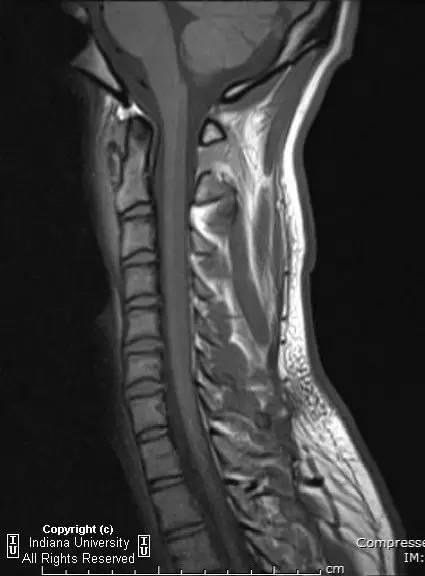

【影像学表现】

CR: C1侧块相对C2侧块外侧移位约5 – 6 mm,符合Jefferson骨折。椎体周围软组织明显肿胀。MR: 椎体周围间隙可见血肿。覆膜完整。寰枕前韧带断裂。寰枢前韧带完整。左侧横韧带从C1侧块的内侧分离,CT对应在C1侧块内侧见小撕脱骨折。翼状韧带完整。寰枕后韧带完整。前纵韧带和后纵韧带完整。黄韧带完整。

Jefferson骨折(Jefferson fracture)是前后弓均累及的C1环粉碎性骨折。Jefferson骨折为头顶受打击并轴向载荷的结果,力从颅骨经枕骨髁传递到颈椎,C1侧块在枕骨髁和C2上关节面之间被压缩,基于侧块的形状产生向心力而导致C1爆裂骨折。齿状突开口位或冠状位重建CT图像应仔细观察双侧C1和C2关节侧块间有无偏移。虽然C1侧块相对C2上关节面侧方移位提示存在骨折,但在X线片上有时难以发现骨折线。MR可显示相应的韧带损伤。

警告:C1异常时单侧或双侧寰枢椎侧方偏移可达2 mm,而Jefferson骨折通常偏移3 mm或以上。